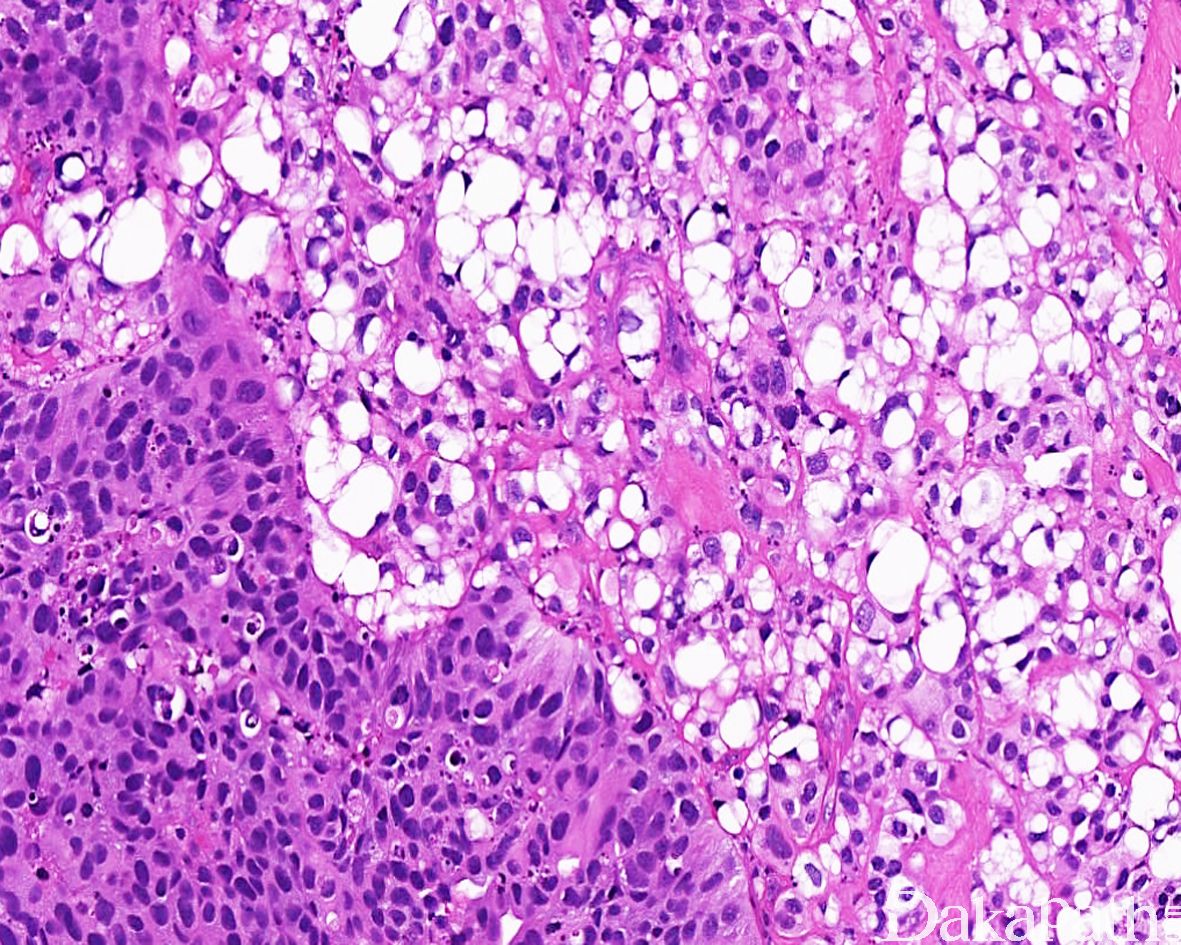

浸润性尿路上皮癌,富脂质

Infiltrating urothelial carcinoma, Lipid-rich

尿路上皮癌瘤细胞胞浆内存在多个空泡挤压核形成类似于脂肪母细胞的瘤细胞

特征性形态学改变是存在大的脂肪母细胞样细胞,具有 1 个或多个胞浆空泡,挤压细胞核;

常和其它类型或普通型尿路上皮癌混合存在,脂质细胞通常占肿瘤成分的 10%-50%,